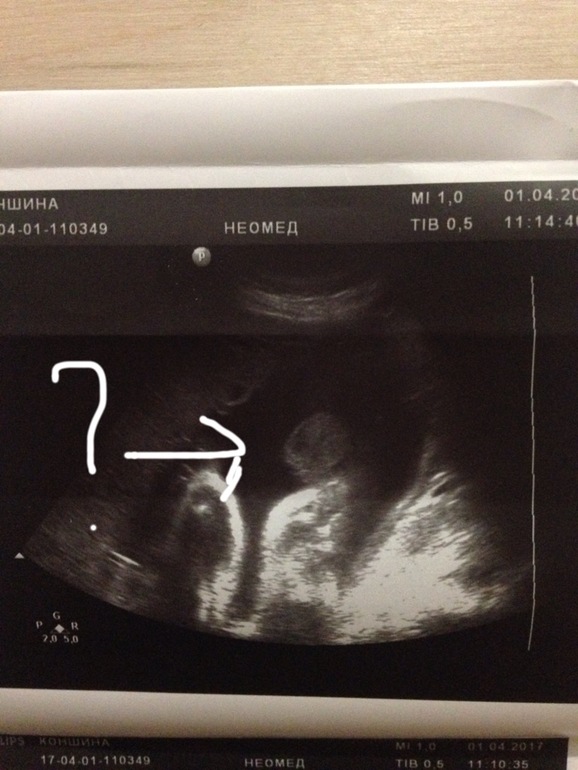

Вопросы про УЗИ, обследования и анализы: что, где, как, когда?Всем привет!) я сейчас на 33 неделе беременности, в 20 и 30 недель сказали, что скорее всего будет девочка, а в 32 - мальчик. На фото не очень понятно) помогите понять)

Мне уже самой кажется, что хорошо видны яички в том месте, куда стрелка указывает. Кому верить - не знаю(

Врач утверждала, что это его мошонка) а сам писюнчик не виден) а я теперь вся в раздумьях)))